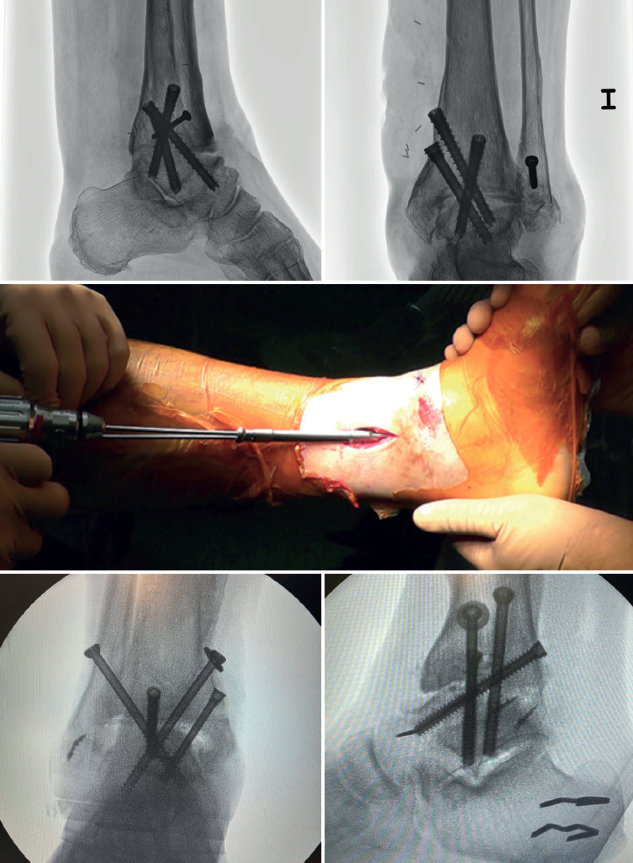

Métodos de fijación

En las artrodesis de tobillo por vía artroscópica, el uso de tornillos a compresión colocados de forma percutánea es la técnica de elección (Figura 5).

La mayoría de los autores consideran el uso de tornillos canulados (de 3 a 4) como el método idóneo de fijación. Los diámetros de los tornillos escogidos oscilarán entre los 6 y los 7 mm. Con esta técnica se consigue del 85 al 100% de fusión y entre el 84 y el 95% de satisfacción del paciente(19).

Van Dijk, Kerkhoffs et al.(20) reportan excelentes resultados con el uso de 3 tornillos como método estandarizado para las artrodesis de tobillo.

Configuración y colocación de los tornillos

Dependiendo de la deformidad y en función de la planificación preoperatoria, se realiza la colocación de los tornillos, comenzando con el tornillo de compresión que contrarresta la deformidad.

Es decir, en las artropatías con componente de varo empezaríamos por un tornillo lateral, mientras que en las desalineaciones en valgo la recomendación es colocar el primer tornillo desde medial. El segundo tornillo debería ser del lado opuesto al primero. Ambos deben realizar la compresión adecuada entre superficies articulares(17).

En general, se utilizan un mínimo de 3 tornillos. El tercer tornillo es el denominado home run, cuya importancia destacan en su trabajo Holt et al.(21). Se dirige cruzando el tobillo desde la parte posterior de la tibia hasta el cuello del astrágalo. Puede utilizarse un cuarto tornillo a modo de aumentación del primero, del que contrarresta la deformidad principal.

Goetzmann et al.(22), en su serie de revisión de 111 casos, respaldan el uso de al menos 3 tornillos para la fijación de la artrodesis tibioastragalina artroscópica. Añadir un tercer tornillo parece asociarse con un menor riesgo de pseudoartrosis y un menor tiempo de consolidación. Estos efectos pueden atribuirse a una mayor estabilidad del constructo.

Glick, Myerson(23) et al. publicaron que la configuración que conferiría mayor rigidez a la osteosíntesis es con 2 tornillos desde medial y 1 desde lateral.

En aquellos casos donde existe una traslación anterior de astrágalo, es importante una buena resección del maléolo posterior tibial para permitir su reducción y posicionar bien al astrágalo. Otra técnica útil es, en decúbito supino, colocar un soporte bajo la tibia distal dejando el talón libre para poder desplazarlo manualmente a posterior.

En algunos de estos casos con traslación anterior del talo, a diferencia de las recomendaciones habituales, puede ser útil posicionar primero el tornillo posteroanterior con rosca parcial, para reducir el astrágalo de anterior a posterior y alinearlo con el eje longitudinal lateral.

Se toman radiografías definitivas anteroposterior, de mortaja, lateral del tobillo, dorsoplantar y oblicua del pie para confirmar la correcta reducción, la posición y la longitud de los tornillos, en especial del tornillo home run (Tabla 3).